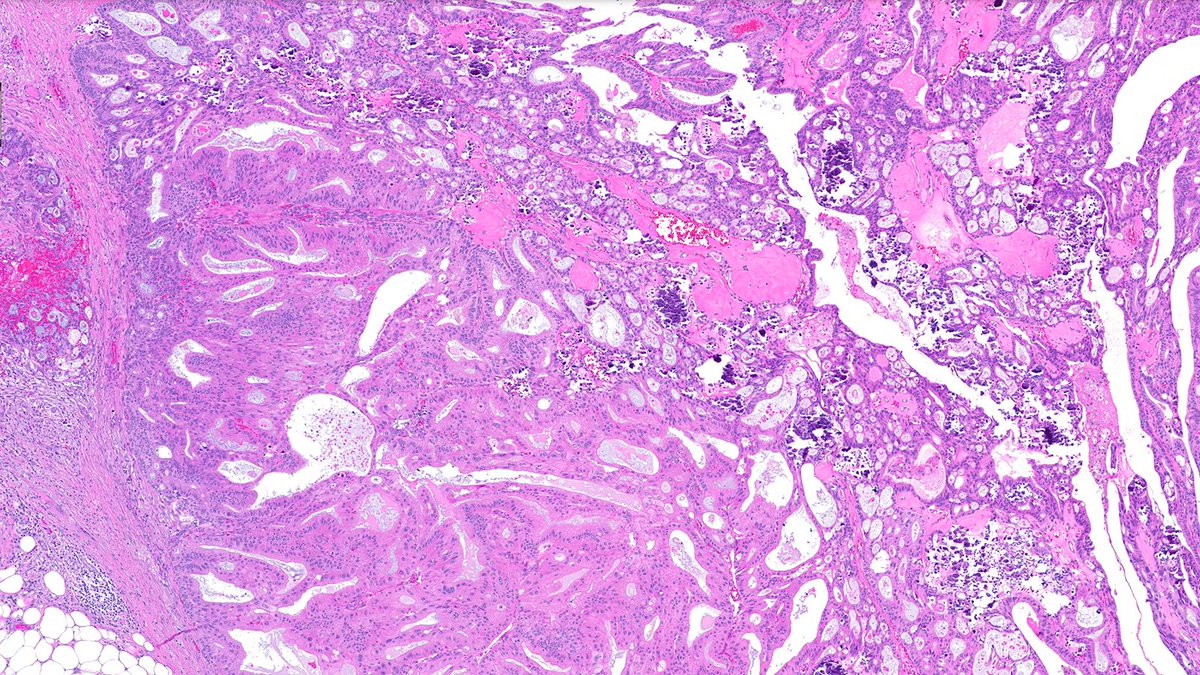

🔔 Answer Reveal! This myxoid mystery 🪼🔬 was… 🥁 Matrix-producing metaplastic carcinoma! 💥🦴 CAM5.2 shown below 👇. Note the markedly atypical focus with glandular differentiation and abruption transition to chondroid 👀 #PathQuiz #PathX #PathTwitter #breastpath